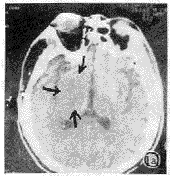

图1 左偏瘫1.5h,CT平扫显示右侧豆状核密度降低与白质一致(豆状核征,往箭头所示)(a),2d后复查,右豆状核区显示明显低密度影(b)。

幕上209例,大脑中动脉供血区197例,大脑前动脉供血区8例,大脑后动脉供血区4例,右小脑半球1例。CT征象阴性40例,致密动脉征表现为平扫CT图像上脑动脉密度增高,超过脑皮质密度,低于钙化密度。豆状核征表现为豆状核轮廓模糊,密度与脑白质一致或稍低(图1)。脑岛带征表现为脑岛带区灰白质界面模糊,灰白质密度一致(图2)。低密度灶分腔隙性(<1cm为小腔梗,1~1.5cm大腔梗)和片状(>1.5cm)。占位征表现为邻近脑室、脑池、脑沟变小(图3)。皮质征表现为皮质局限性密度减低,与脑白质密度一致(图4)。各征象在不同时间出现率见表1,敏感性等指标测定结果见表2。